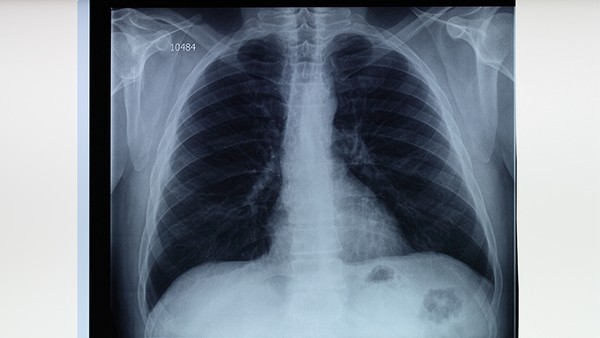

胸片正常不能完全排除结核,需结合痰涂片检查、结核菌素试验和γ-干扰素释放试验三项检查综合判断。